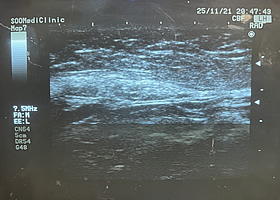

초음파 및 시각적 진단으로 지방의 분포와 피부 탄력도를 확인합니다.

3D 입체 초음파로 피부, 피하지방층, 근육, 신경 등 연부 조직의 위치와 두께 측정